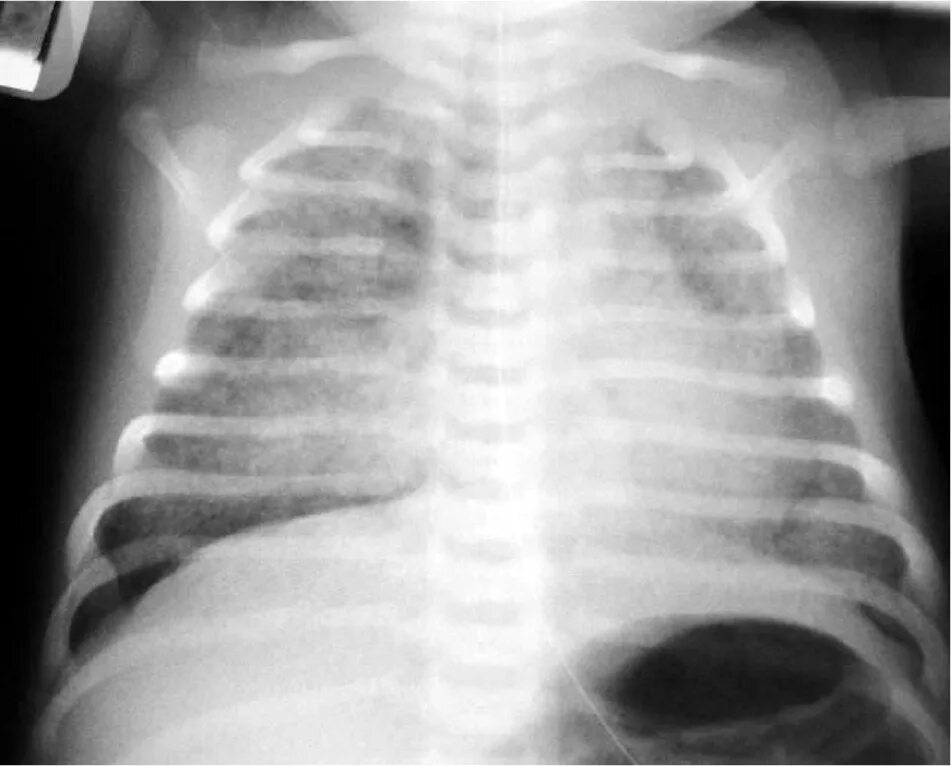

Синдром аспирации